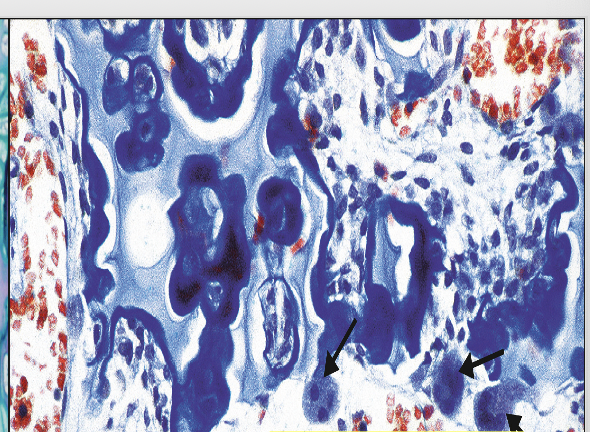

What does this image show

Provisional fracture callus, note zonation.